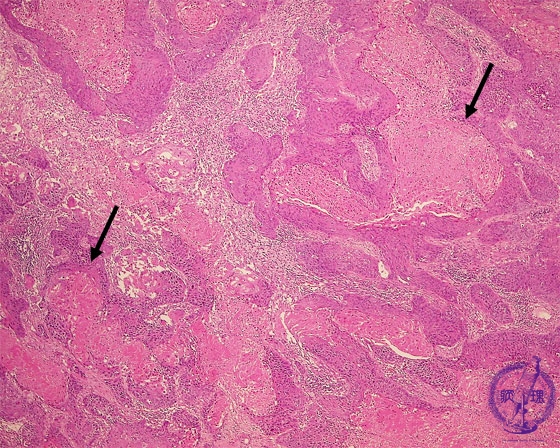

非小細胞肺癌(扁平上皮癌)ミクロ像(HE弱拡大)

ミクロ像(HE弱拡大):腫瘍は不規則地図状に増殖している。角化壊死像(矢印)も目立つ。腺癌と異なり明らかな腺腔形成は見られない。